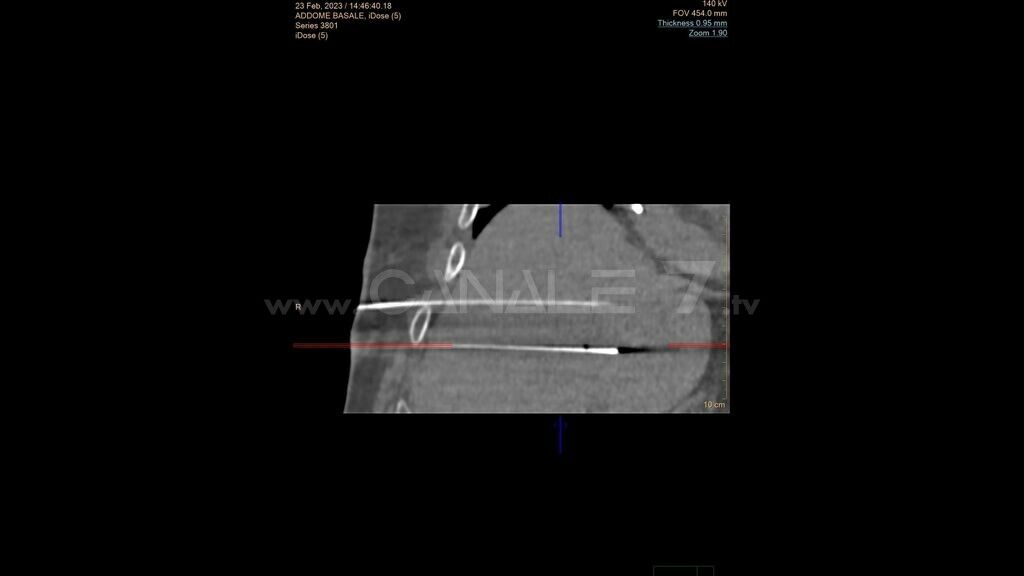

Si tratta di una nuova tecnica di distruzione dei tumori collocati in sede non diversamente trattabili perché vicini a strutture vascolari o biliari ed è eseguita con l’ausilio della tac e di un robot.

E’ stato eseguito con successo all’Istituto Nazionale di Gastroenterologia “S. de Bellis” di Castellana Grotte il primo intervento in Italia di radiologia interventistica assistito dal robot. Tecnicamente si chiama procedura di elettroporazione irreversibile con tecnica stereotassica robotizzata TC: si tratta di una nuova tecnica di distruzione dei tumori collocati in sede non diversamente trattabili perché vicini a strutture vascolari o biliari ed è eseguita con l’ausilio della tac e di un robot. L’apparecchio di navigazione stereotassica robotizzato acquisito dal “de Bellis” è il primo impianto in Italia e consente di migliorare la precisione e la sicurezza dei trattamenti percutanei mini invasivi in ambito oncologico. Questa procedura è stata impiegata su un paziente di 72 anni, già operato per un voluminoso tumore del fegato, che aveva sviluppato una recidiva maligna non suscettibile di intervento chirurgico né di trattamenti ablativi termici proprio per la collocazione “critica” dovuta alla vicinanza di strutture vascolari.